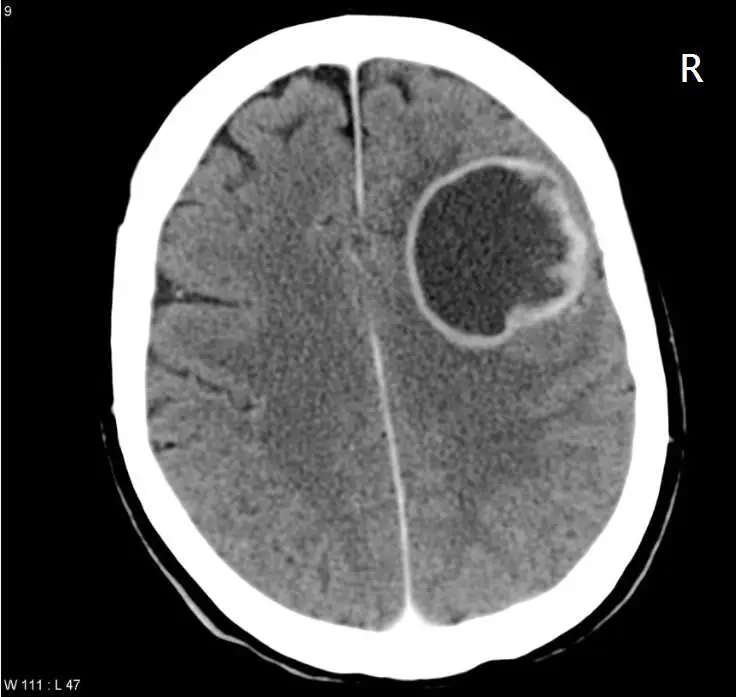

影像與前題相同,為腦部橫斷面 CT 掃描(W111: L47),右上角標示「R」代表影像右側對應患者解剖右側。

- 病灶位置:右側大腦半球(影像圖面偏左,「R」標記的同側),位於右側頂葉至顳葉交界區的腦實質內

- 病灶特徵:大型圓形指環狀病灶(直徑約 4–5 cm),具有高密度環形包膜、中央低密度膿腔及周邊血管性水腫

- 佔位效應:右側大腦半球受壓,中線輕度向左偏移

關鍵判讀:病灶位於右側大腦半球,依據「神經交叉支配」原則,右側運動皮質及皮質脊髓束(corticospinal tract)在延腦的錐體交叉(pyramidal decussation)後,下行控制左側肢體的運動功能。因此右側大腦半球的佔位性病灶將造成左側偏癱。